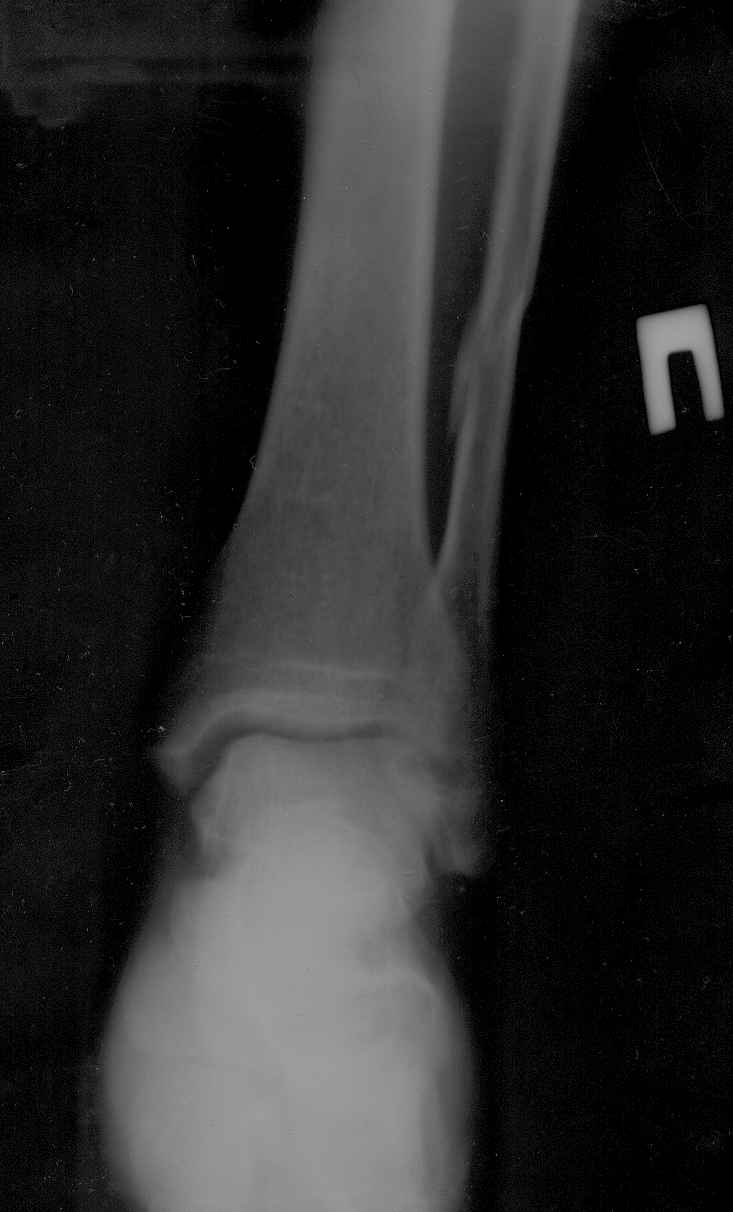

ПЕРЕЛОМ Н/ЛОДЫЖКИ

У пациента возраст 58лет закрытый перелом н/лодыжки почти без смещения и н/3 малоберцовой кости со смещением правой голени.

из сопутствующих-рассеяный склероз, ибс, гипертоническая болезнь. ro-снимки прилагаются. подскажите оптимальный метод лечения